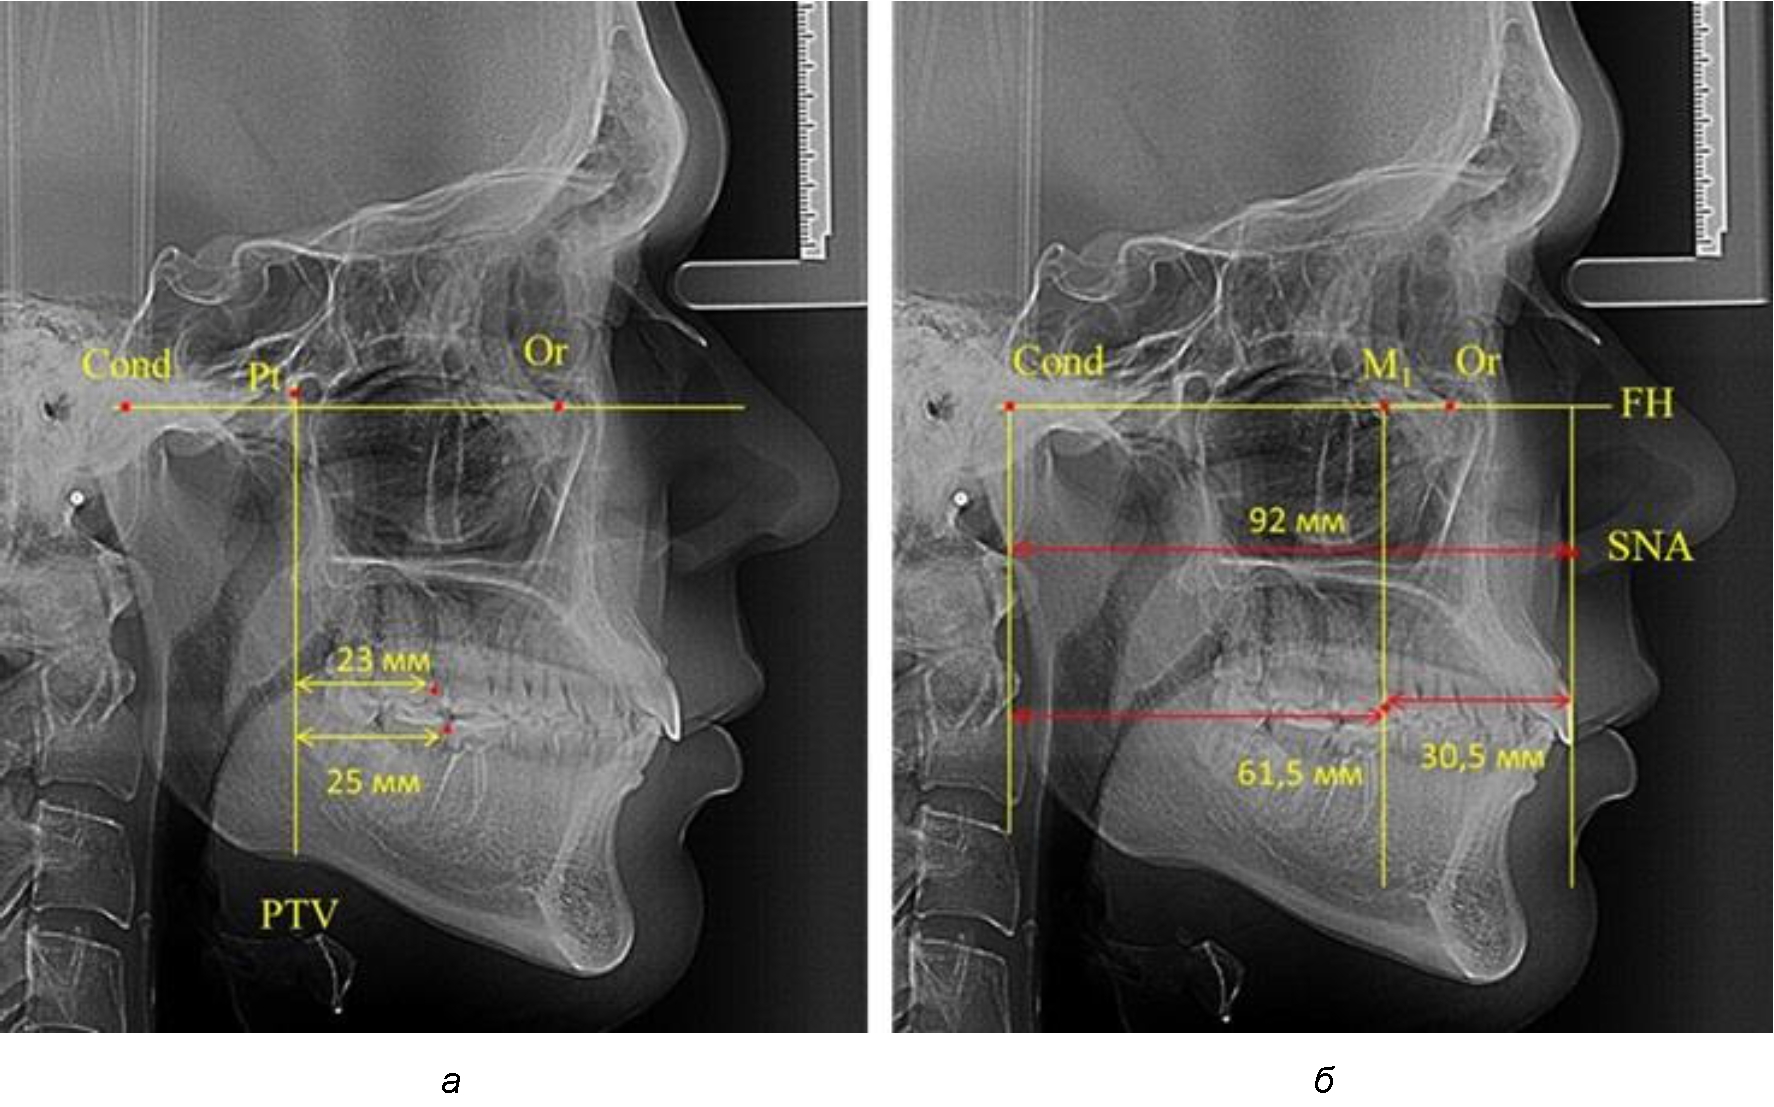

После прорезывания вторых постоянных моляров кондилярно-спинальный увеличивался до 80 мм.

Дистальная поверхность первого постоянного моляра отстояла от крыловидной вертикали на величину, составляющую около 18 мм, что, так же, как и в предыдущих периодах прикуса, было близким по значению к данным R. E. McDonald, а именно возраст, плюс 3 мм.

Обращает на себя внимание отношение глубины гнатического отдела лица к дистальному отделу, а именно к кондилярно-молярному расстоянию, которое, вне зависимости от сагиттальных размеров, составляло 1 : 1,5.

Рентгенограмма 16-летнего ребенка, с реперными линиями и анализируемыми линейными параметрами по двум используемым методам, представлена на рис. 6.

Рис. 6. Особенности положения первых моляров по R. E. McDonald (а) и по предложенному методу (б) у ребенка 16 лет